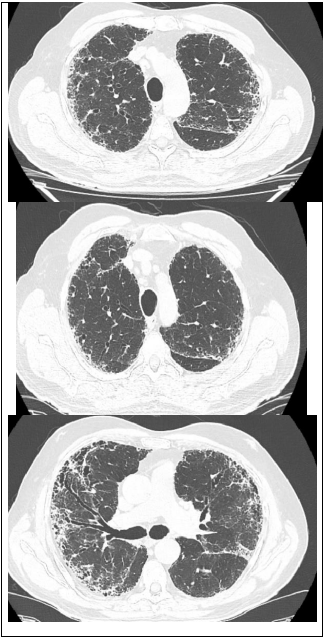

Leia o caso a seguir para responder às questões de 22 a 24.

Paciente 68 anos de idade, do sexo masculino, refere dispneia progressiva há 2 anos, inicialmente aos grandes esforços e atualmente aos pequenos esforços, associado com tosse seca frequente. Nega outros sintomas associados.

Ex-tabagista de 10 maços-ano, cessou o hábito há 20 anos.

Criou 2 pássaros em gaiola, em casa por 2 anos, cessou há 15 anos.

Trabalha em escritório de advocacia por toda a vida. Nega contato com mofo. Nega uso de medicações contínuas prévias ou atuais.

Ao exame em bom estado geral, leve dispneia, baqueteamento digital, IMC: 20, FR: 24irm, FC: 90 bpm, PA: 120x80mmHg, spO2 90% em ar ambiente. Ausculta pulmonar: estertores finos em velcro bibasais. Sem outras alterações.

Traz resultado de exame:

FAN negativo, FATOR REUMATÓIDE negativo

Espirometria: distúrbio ventilatório restrivo acentuado.

Tomografia de tórax: padrão típico de PIU (pneumopatia intersticial usual).

Qual é o diagnóstico mais provável para o paciente?